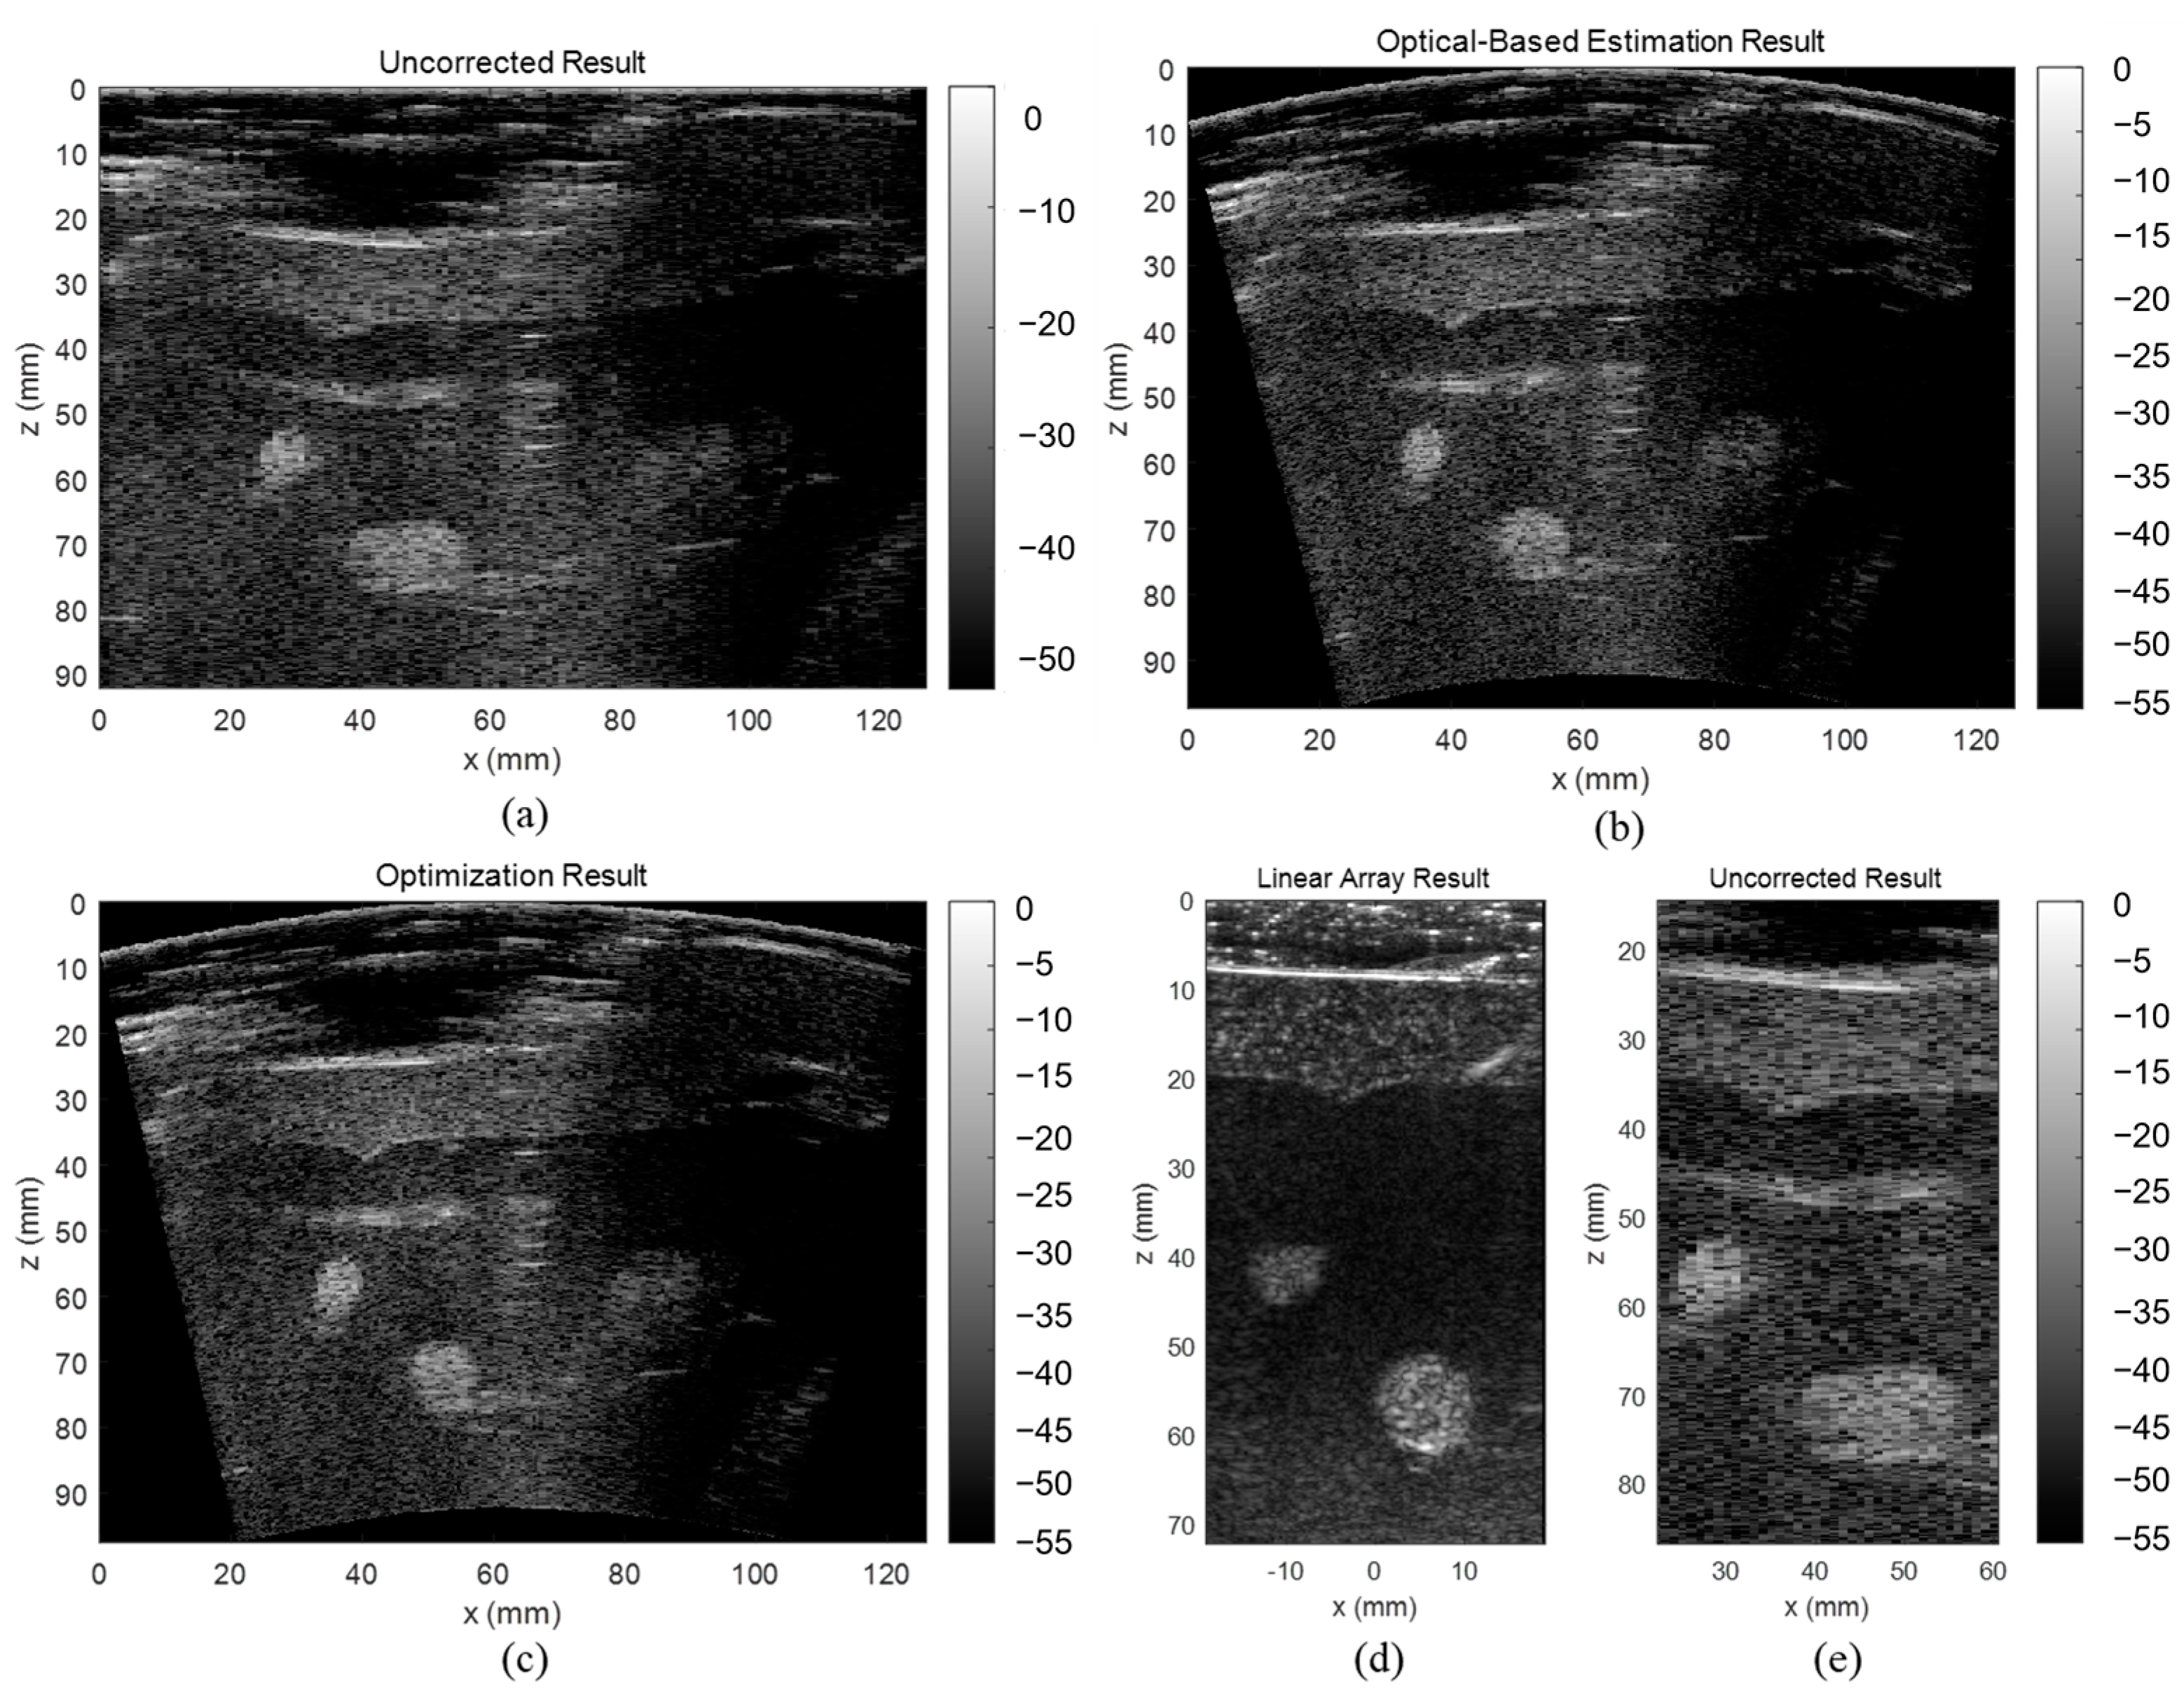

3.2. CIRS Phantom Results

The uncorrected, optical-based estimation, and optimization results of the CIRS phantom are shown in Figure 9. The results illustrate that without any correction on array shape, the reconstructed image will have strong defocusing and distortion, while both proposed algorithms can correct these effects. The lateral FWHM of the point scatters in different depths are plotted in Figure 9d. The averaged lateral FWHM of the uncorrected, estimation, and optimization results are 6.04 mm, 2.42 mm, and 2.75 mm, respectively. The aspect ratio, CNR, and GCNR of the center hyperechoic cyst and the second left anechoic cyst are listed in Table 4. Both corrected results have significantly lower distortion and higher contrast than the uncorrected result. Specifically, analyzing the cysts in the CIRS phantom, the optimization result has a more accurate shape, clearer boundary, and higher contrast compared with the optical-based estimation result. Therefore, it is believed that the shape optimization algorithm has the overall best performance on estimating the array shape.

Figure 9.

Reconstructed images of the CIRS phantom (a) without array shape correction, (b) with optical-based estimated shape, and (c) with optimized shape, and (d) line plot of lateral FWHM of the point scatters.

Table 4.

Evaluation Results of the Hyperechoic Cyst in the CIRS Phantom.